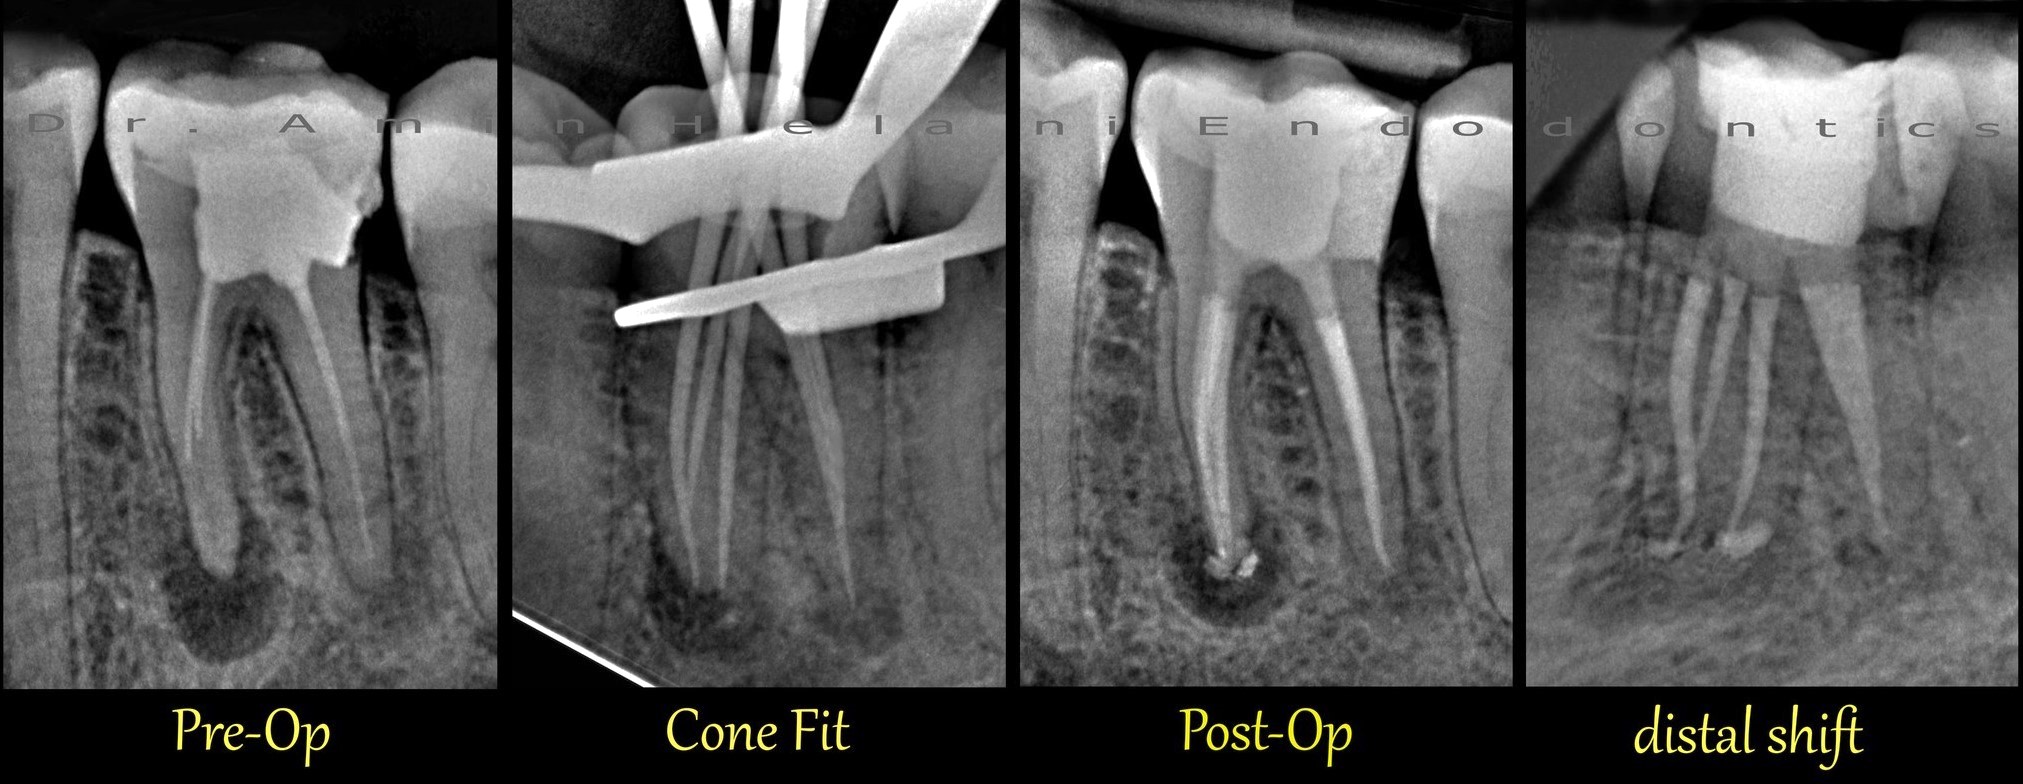

Gekrümmter Kanal im unteren Molaren